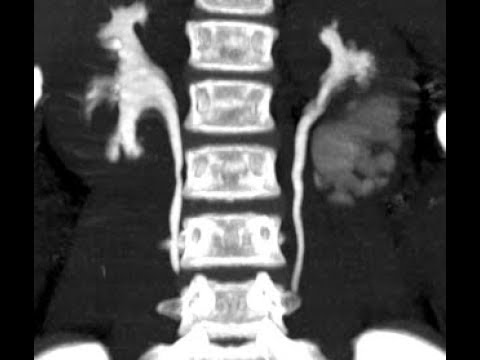

Bladder exstrophy repair (Dr. Kureel) Epispadias repair (Dr. Sripathy) Hypospadias repair (Dr. Panjwani) Lap pyeloplasty (Dr. VVSS Chandrasekaram)

There were 3 symposia: Neurogenic bladder/ UDS, antenatal hydronephrosis and disorders of sexual differentiation. There were three panel discussions: vesico ureteric reflux, hypospadias and posterior urethral valves. Day 2 had free paper session. Thirty papers were presented and four PGs were awarded medals and prize paper certificates. PG quiz was well attended and two PGs were awarded medals. During the inauguration on Day 1, medical students who won pediatric surgery quiz were awarded cash prize by the dean. Ebooks of urodynamic manual and PAEDUROCON2017 souvenir were released during the inauguration.